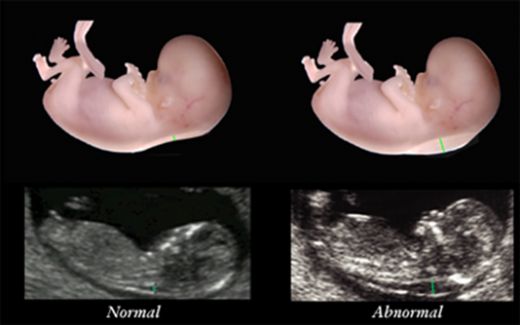

2. Tanı Yöntemleri Down sendromunun tanısında kullanılan çeşitli yöntemler bulunmaktadır:

Tarama Testleri: Gebelik boyunca yapılan tarama testleri, Down sendromu riskini belirlemede kullanılır. Ancak bu testler sadece risk derecesini gösterir ve kesin tanı koymaz.

Amniyosentez: Kesin tanı için amniyosentez gibi invaziv testler gerekir. Amniyosentez, bebeğinizin genetik yapısını inceleyerek Down sendromu gibi durumları kesin olarak belirleyebilir.